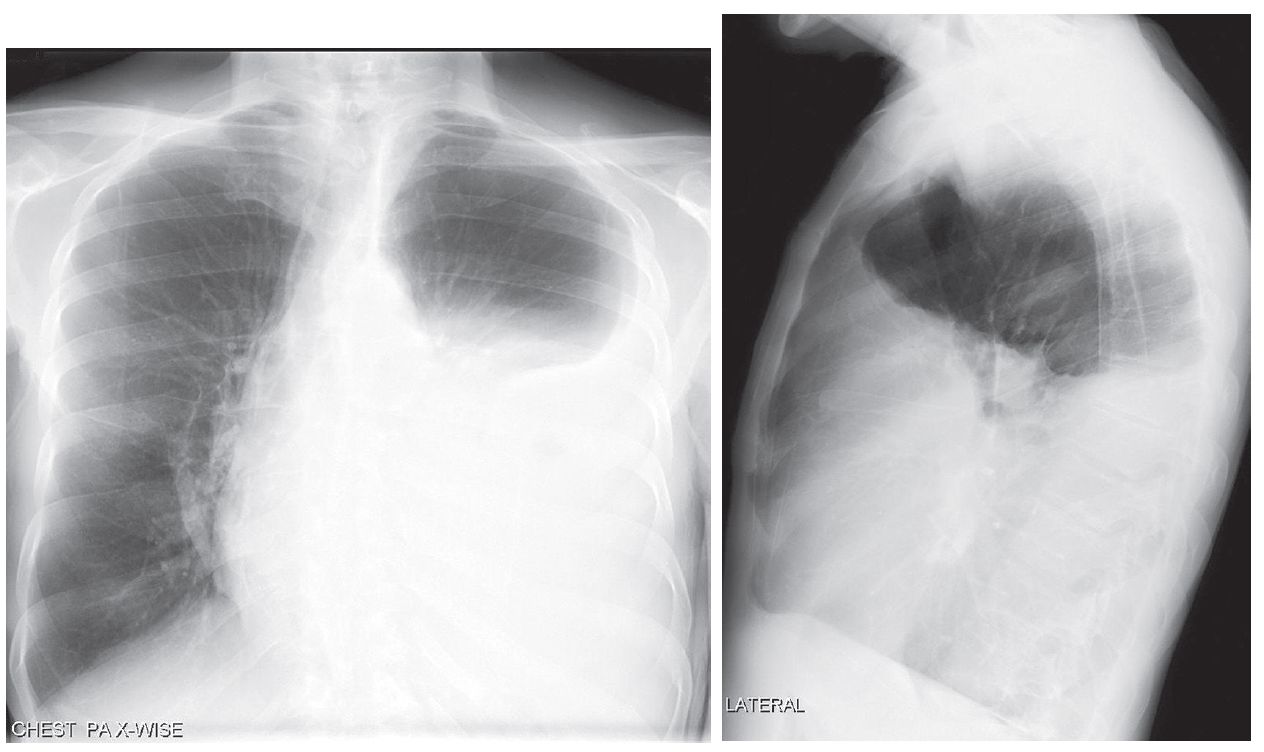

PA and lateral chest X-rays show opacification of nearly two-thirds of the left hemithorax. Note the airless left mid- and lower thorax and contralateral mediastinal shift from this pleural space-occupying process.

The lateral exam also demonstrates a positive spine sign characterized by increased opacity over the lower thoracic spine and obscuration of the left diaphragm.

If atelectasis is secondary to massive pleural effusion, as in this case, the affected hemithorax is dull to percussion with diminished breath sounds on auscultation.